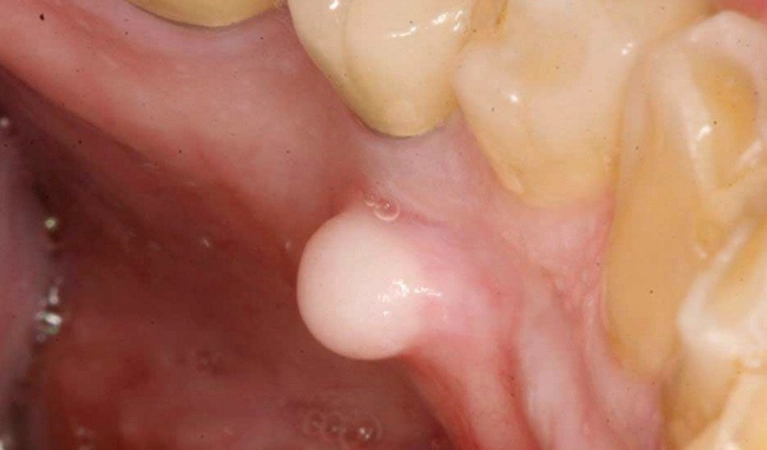

- Mucoceles: This is a classic one. It's a fluid-filled sac that forms when a tiny salivary gland duct gets blocked or injured (think: biting your cheek or lip). It often looks bluish, clear, or like a soft, movable bubble. They're squishy, not hard. They can hang around for weeks but often rupture and heal on their own.

- Irritation Fibroma: This is the body's overzealous healing response. If you chronically bite or rub an area (maybe from a rough tooth or dental appliance), your body might lay down extra collagen fibers, forming a firm, smooth, pink lump. It's basically a scar. It won't go away on its own, but it's harmless.